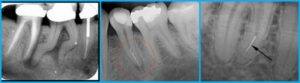

- Специфическое строение корня. Условие успешного лечения – полностью запломбированная корневая система. Некоторые ответвления из-за нестандартного строения апекса не видны даже на рентгеновском снимке, и тогда стоматолог не застрахован от совершения ошибки.

Методика лечения боли в зубе с удаленным нервом зависит от причин, которые вызвали это состояние. Стоматолог проведет осмотр, при необходимости назначит рентгенологическое исследование.

После детального осмотра и опроса врач назначит дальнейшее обследование. Чаще всего необходимо сделать рентген той области, где сосредоточены неприятные ощущения, чтобы просмотреть состояние пульпы, каналов, обнаружить внутренние кариозные полости.

Особое внимание обращают на состояние корня, наличие микротрещин в нём, поскольку такие трещины всегда становятся сосредоточием бактерий. Для лечения может понадобиться удаление пломбы или снятие коронки.

Если воспалился корневой канал, то стоматолог выполняет вторичное препарирование элемента с очищением корневых каналов, закладыванием в них лекарственных средств и пломбированием. Перед вмешательством пациенту чаще назначается рентгенологическое исследование, чтобы исключить наличие дополнительных корней или их искривление.